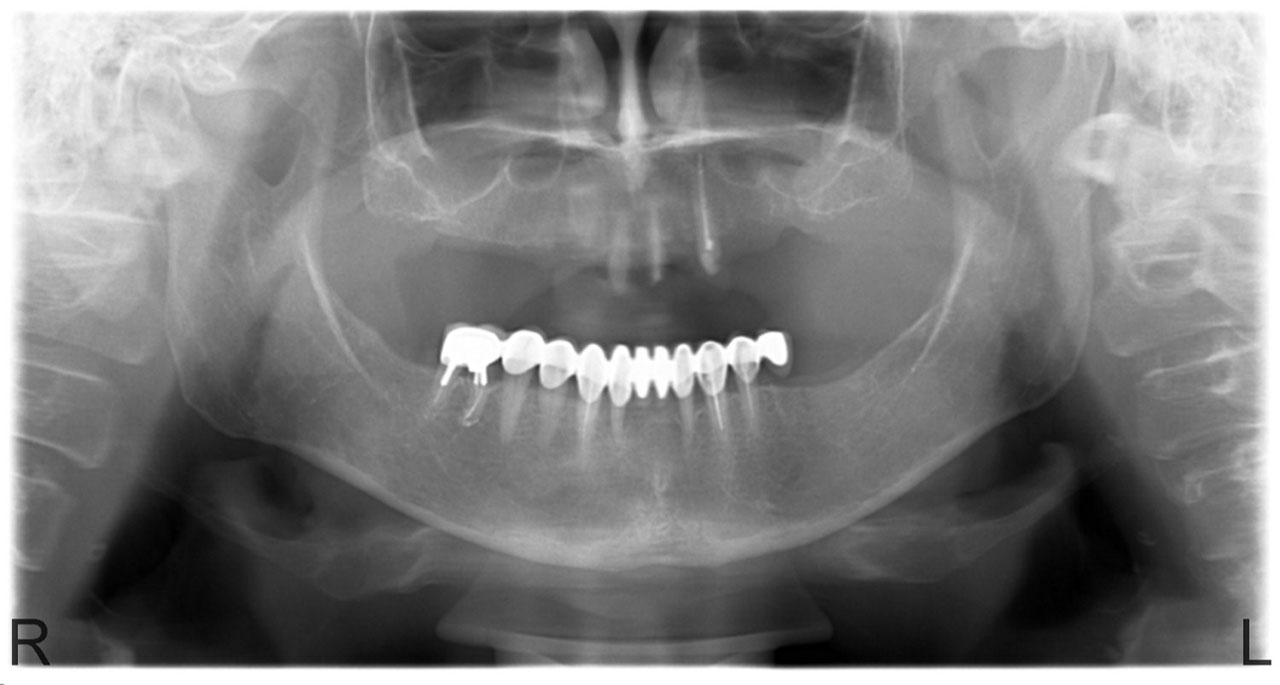

Teljes fogatlanság.

• esettanulmany-14

Alsó- felső fogatlan állcsont teljes implantációs helyreállítása.